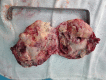

Extra-gonadal mature teratoma: A case report of retroperitoneal location with a literature review

Extra-gonadal mature teratoma is a benign tumor occurring rarely in adults. The retroperitoneal localization constitutes less than 4%. Treatment consists of surgical resection. Histological examination is essential for definitive diagnosis. We reported an unusual case of mature retroperitoneal teratoma discovered in a young man with abdominal pain.